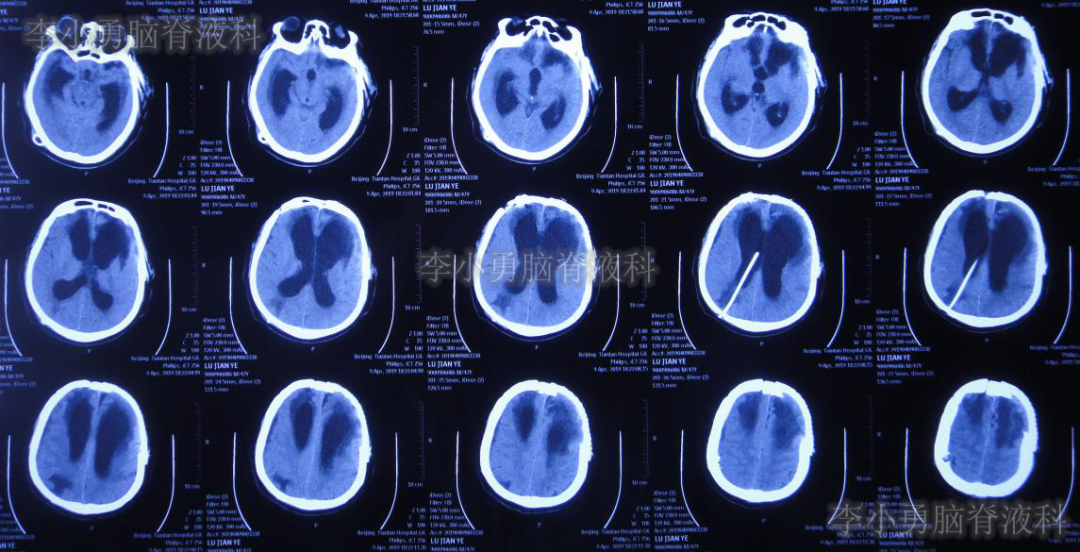

经过2个月治疗,即2019年9月30日即脑室引流术后55天时,行脑室-腹腔分流术。

分流术后10天,即2019年10月9日,饮食变正常,神志完全清楚(图-18),常规给予复查头颅CT(图-19)示脑室进一步缩小。

图-18:2019年10月8日

图-19:2019年10月9日头颅CT脑室进一步缩小

出院后54天即2019年12月9日,复查头颅CT示脑室进一步缩小。患者智力、走路变得基本正常,但存在情感(喜怒哀乐不能表达)缺失,言语少(图-20)。

图-20:头颅CT脑室再次进一步缩小